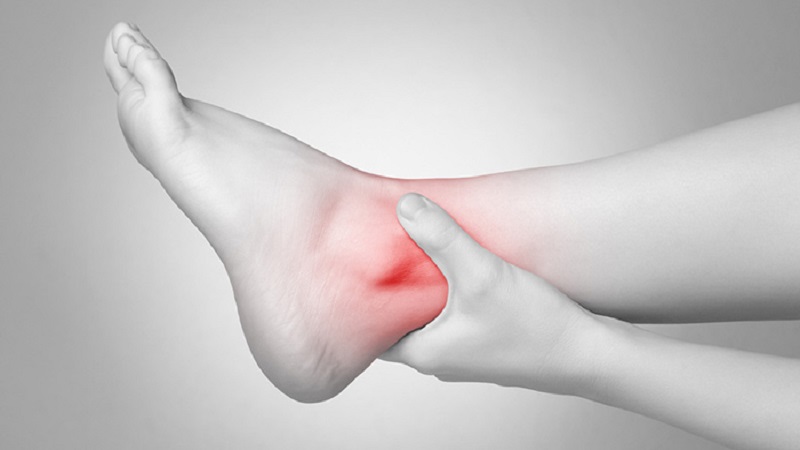

پیچ خوردن و رگ به رگ شدن مچ پا: علت و درمان

پیچ خوردگی و رگ به رگ شدن مچ پا عارضهای است که ناشی از آسیب نوارهای بافتی سفت به نام رباط یا لیگامان است که استخوانهای پا و ساق پا را احاطه و بههم متصل کردهاند. این عارضه معمولا هنگامی که پا و یا مچ پا به طور ناگهانی و به طرز ناخوشایند میچرخد رخ میدهد. پیچ […]

علت درد مچ پا چیست و چگونه درمان میشود؟

مچ پا دارای مفصل لولایی است و قسمتی است که پا و ساق پا به هم می رسند. این بخش از سه استخوان تشکیل شده است: درشت نی، نازک نی و تالوس. مچ پا توسط شبکه ای از رباط ها و تاندون ها احاطه شده است. معمولا فشار زیادی به مچ پا وارد می شود و به […]